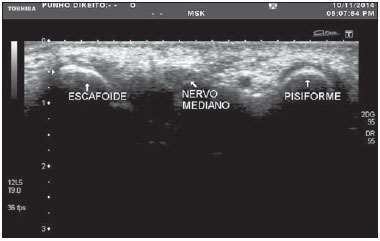

Caso clínico 5 para a questão 30.

O.P.N, 60 anos, sexo feminino, costureira, obesa, hipertensa, diabética e moradora de Tracunhaém-PE, é encaminhada ao consultório de neurocirurgia com queixa de dor, dormência e formigamento em punho e dedos da mão direita que piora no fim do dia há 06 meses e com perda de força há 01 semana. É destra e relata episódios semelhantes nos últimos 06 meses, em especial quando precisa trabalhar muito. Trouxe resultado de ultrassonografia do punho direito com o diagnóstico de Síndrome do Túnel do Carpo (STC).

Assinale a alternativa INCORRETA.

Provas